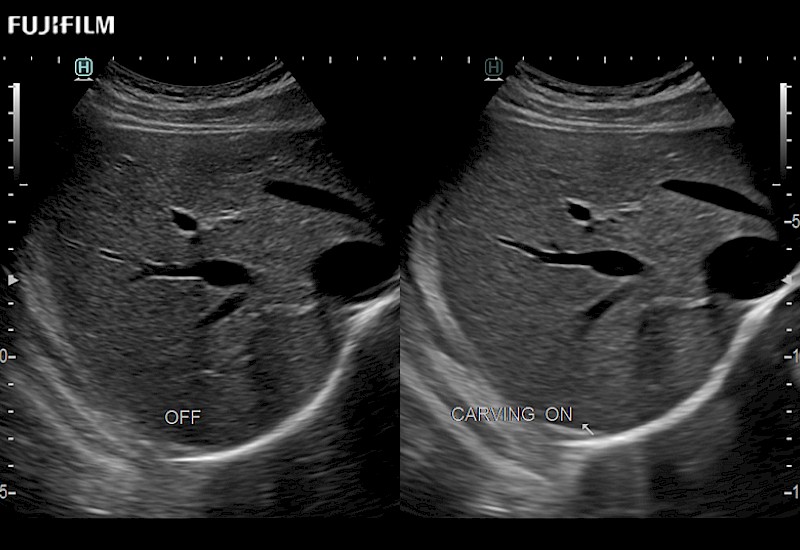

Our dedication to Laparoscopic Surgery allows us to offer superior image quality, outstanding system reliability and intuitive use of cutting edge technology.

The ARIETTA 750 incorporates all of the proven technologies and functions that medical professionals have come to expect from Fujifilm Healthcare.

ARIETTA 750 is the definitive diagnostic ultrasound solution for any clinical setting - Private Office, Imaging Center, or Hospital. The ARIETTA platform provides the ultimate in clinical performance with its state-of-the-art features and large user-friendly display.